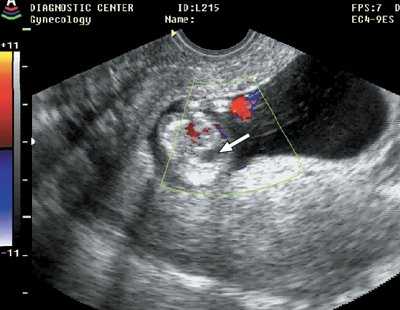

Рис. 4. Гастрошизис (стрелка), беременность 13 недель 1 день.

Рис. 5. Мегацистис (стрелка), беременность 11 недель 3 дня.

Рис. 6. Иниоэнцефалия, беременность 11 недель 6 дней.

Рис. 7. Диафрагмальная грыжа (стрелка), беременность 11 недель 4 дня.

Рис. 8. Дефект межжелудочковой перегородки (стрелка), беременность 12 недель.